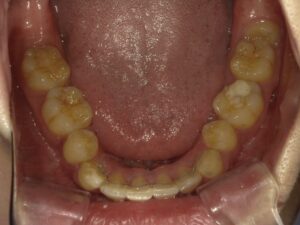

矯正治療が終了しました。

右上の抜いた大きな歯のスペースもしっかり閉じることができ、前歯も綺麗に並んでいると思います。

口元の印象も大きく変わったと、患者さんに喜んでいただけました。